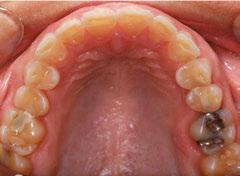

Figures 6 through 9 demonstrate a patient successfully treated with NiTime Aligners following the patient’s rejection of other systems. Figures 6 and 8 display pre- and posttreatment photos of a patient that presented with a Class II malocclusion and normal OB/OJ. This patient has teeth Nos. 7 and 10 missing congenitally. Note that the patient was treated as a child and has a canine substitution due to the missing lateral incisors. Recession was noted on tooth Nos. 2,3, 4, 5, 9, 11, 13, 14, 22, 24, 26, and 27. The patient tried labial and lingual brackets unsuccessfully, as well as a leading clear aligner to correct her malocclusion as an adult. In all three treatments, the patient could not tolerate the mechanics due to increased discomfort and was unable to complete therapy.

It is important to note that there was no refinement required for this case, and the patient finished in 26 weeks with 26 trays. Although the patient presented with significant recession, it did not worsen with treatment. As demonstrated in Figure 9, teeth aligned as planned by the OrthoFX treatment plan shown in Figure 7. Overlays of the actual results with the original treatment plan indicate a high level of predictive accuracy. Not only was a satisfactory result produced from the patient wearing the aligners, but the accuracy is quite high for the NiTime material despite the patient wearing it significantly less than the traditional 22 hours per day.

Figure 9: Overlays of the actual results with the original treatment plan